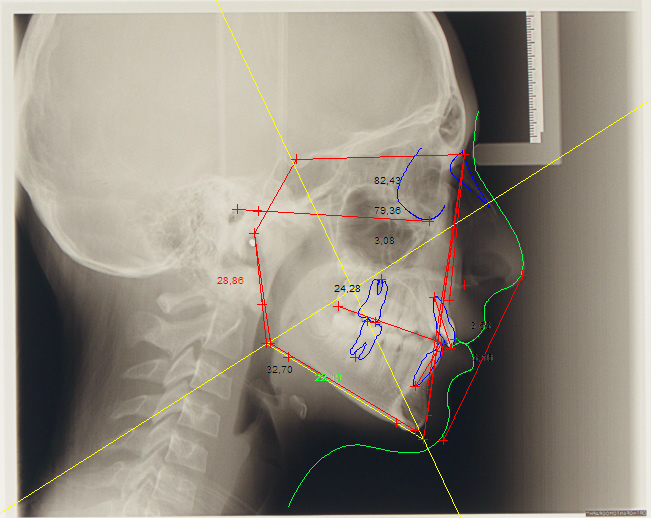

L'Ortodonzia è la disciplina odontoiatrica che si occupa dello studio, della diagnosi e della terapia della posizione anomala di uno o più elementi dentali, per il danno che questa alterazione porta sull'estetica del volto e sulle funzioni della respirazione, masticazione e fonazione. L'ortognatodonzia, più propriamente, è la disciplina medico-stomatologica che si occupa della correzione delle malformazioni dei mascellari (regione anatomica maxillo-mandibolare) e delle alterazioni della crescita e dello sviluppo degli stessi, al fine di determinare una correzione stabile della malocclusione esistente. La pratica ortodontica si avvale di: apparecchiature ortodontiche fisse e mobili, di terapie chirurgiche, di terapie biomeccaniche, del trattamento chirurgico-ortodontico dei denti inclusi e trasposti, dell'ortodonzia dell'adulto e pre-protesica, della contenzione.